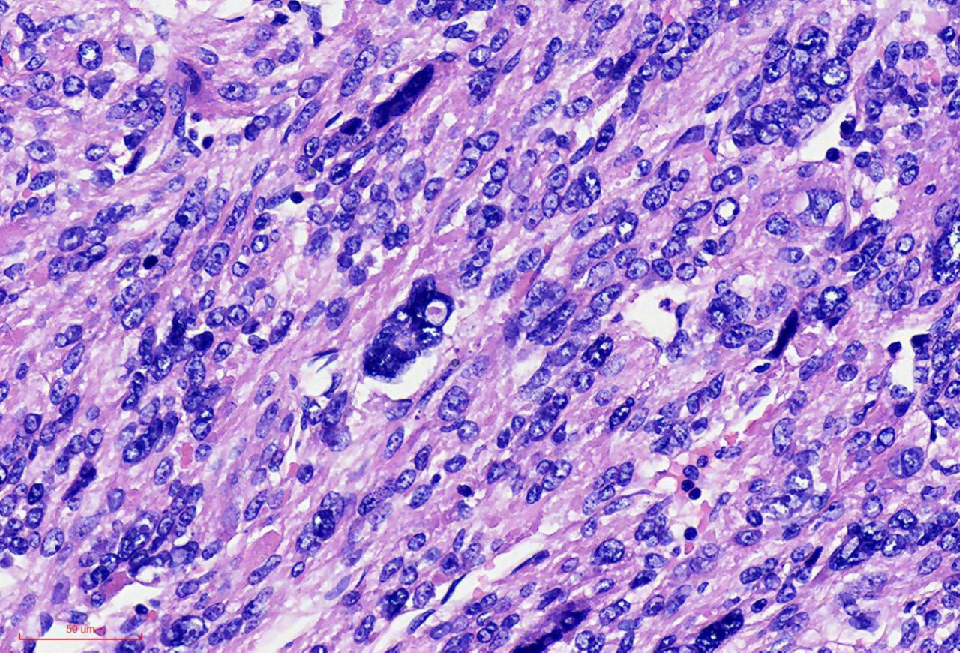

组织学改变

肿瘤境界清楚

细胞丰富

鹿角样/血管外皮瘤样血管

肺水肿样水肿/疏密相间

细胞核奇异,嗜酸性胞质,有显著的嗜酸性核仁,核仁周围可见空晕,部分细胞呈横纹肌样

核分裂象少见

无凝固性坏死

FH表达缺失